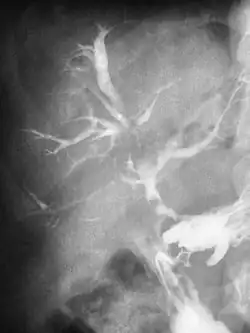

| Duodeno Biliary Fistula | |